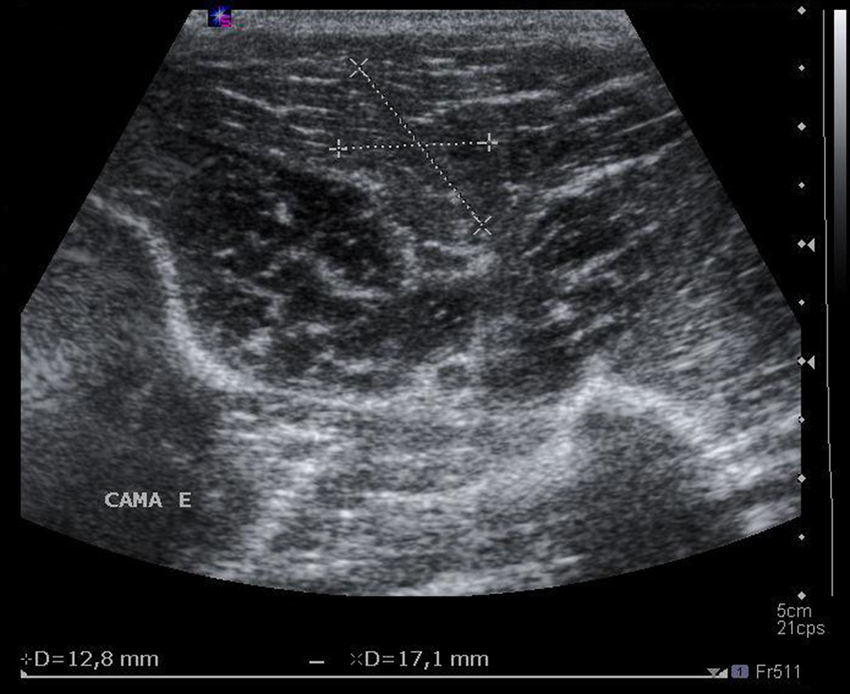

Ultrasonido de Abdomen

Ultrasonido de Partes Blandas